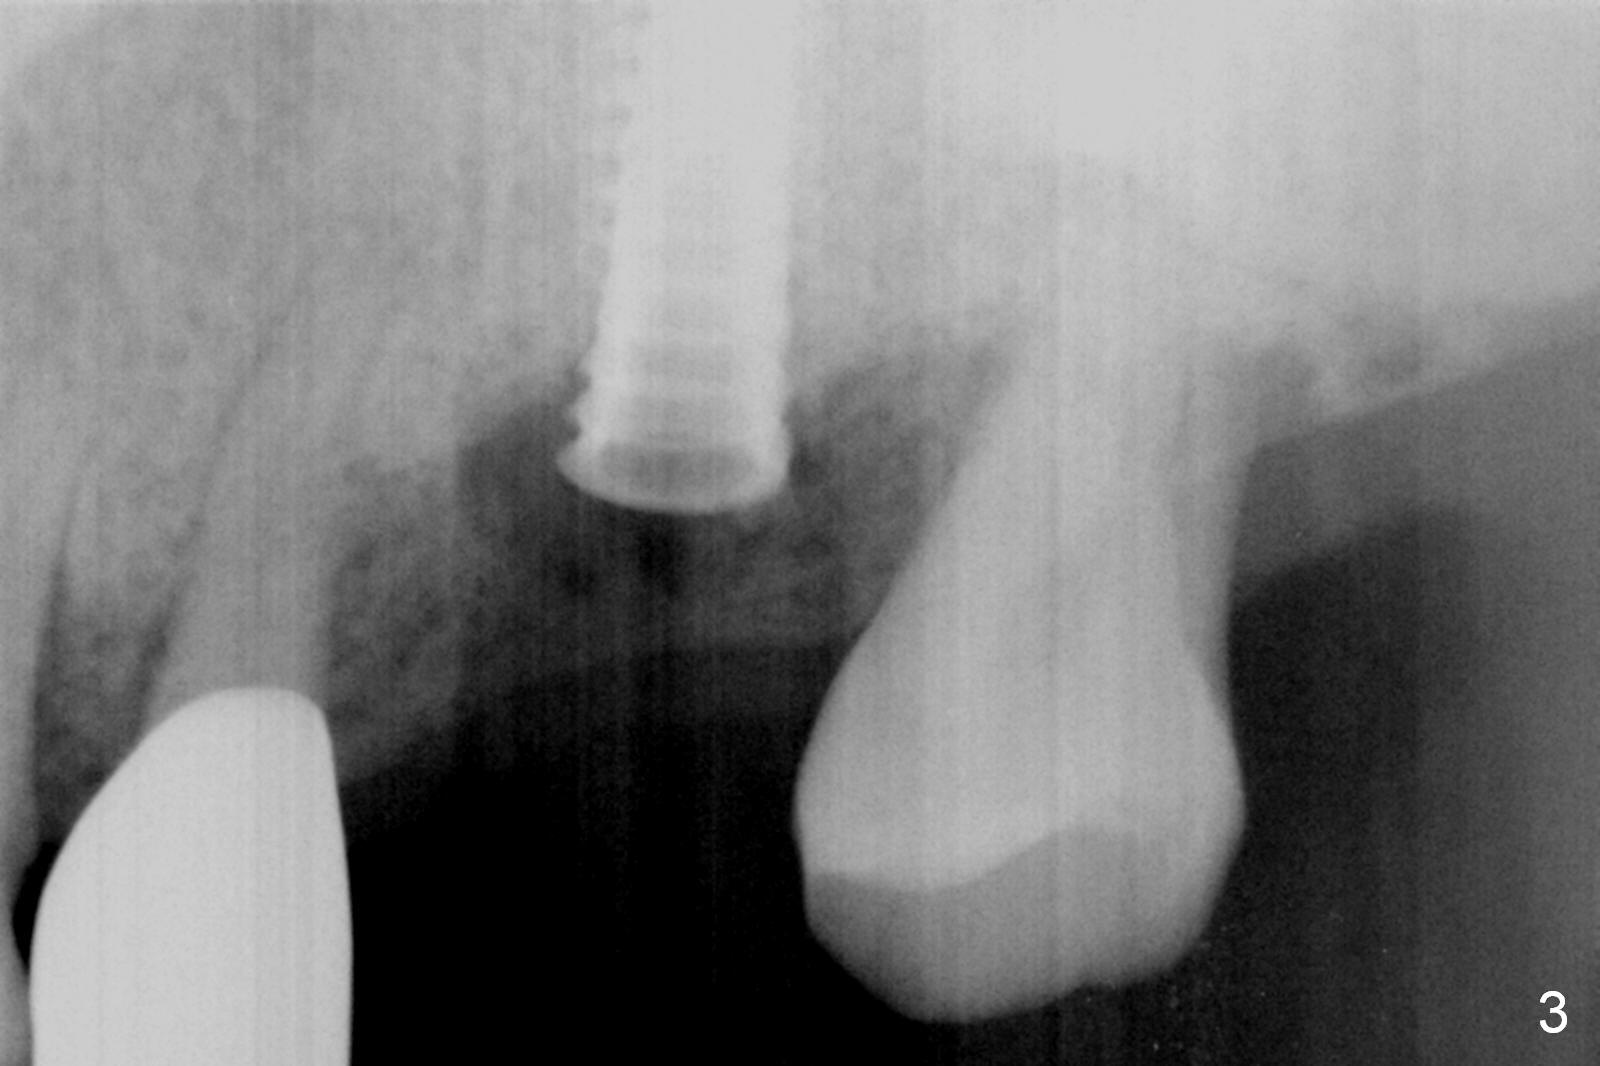

Preop exam show that the tooth #14 appears to be more severe than #18. When the former is extracted with forceps (not so easy), the mesial portion of the mesiobuccal root splits. The latter may be the reason for discomfort and one of the outcomes of advanced peridontitis. The septum is wide enough to use 4.3 mm Magic Drill (MD) following 1.6 mm pilot drill and Marking bur. A 5x13 mm IBS implant is placed apical to the mesial and distal crest and coronal to the septum (Fig.2,3). Insertion torque is ~ 35 Ncm. A 6.0x5.7(4) mm pair abutment is chosen over a 6.5 mm one, because the implant is placed somewhat distally (Fig.4,5). If the implant were placed more apically, the 4 mm cuff would be short for restoration. Allograft and autogenous bone harvested from the MD is placed around the coronal portion of the implant and the abutment cuff (*). Acrylic is spread around the abutment to hold the bone graft in place (without trimming).

The amount of the bone graft mesial and distal the implant seems to reduce 3 and 4 months postop, respectively (Fig.6,7 arrowheads). When the acrylic is cut off 4 months postop, the bone graft is loose. The gingiva is unhealthy. The abutment and implant are loose. A healing abutment is placed (5x4 mm). The implant is torqued to 35 Ncm 6 months postop with the healing abutment reapplied. The patient will return for follow up nearly 9 months postop. A larger healing abutment will be used if the implant is stable. Two weeks later, use a smaller restorative abutment for easy impression. In fact the implant is unstable with #15 mesial shift due to abnormal occlusion with #17 (Fig.8). Bone density around the implant is low (* in Fig.9 (PA), 10,11 (CT sagittal, coronal sections)). A healing screw is placed for self healing. A 2nd option is to remove the implant (Fig.12), BEB (Fig.13) and place the implant deeper (Fig.14) or larger one (5.5-6.5x13 mm). The 3rd option is to place larger and longer implants (Fig.15 (tapered), 16 (cylindrical)). The implant access has partially closed 14 months postop, but there is a small buccal opening with sanguine exudate. Incision reveals severe bone loss around the implant; the mobile tooth #15 is extracted (Fig.17). After debridement and irrigation with normal saline, Vera Graft (Fig.18 *) and Collagen plug are placed with periodontal dressing.